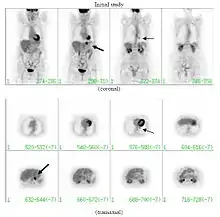

If there is an intermediate risk of malignancy, further imaging with positron emission tomography (PET scan) is appropriate (if available). It can be done simultaneously as a CT scan in the form of PET-CT. Around 95% of patients with a malignant nodule will have an abnormal PET scan, while around 78% of patients with a benign nodule will look normal on PET (this is the test sensitivity and specificity).[15] Thus, an abnormal PET scan will reliably pick up cancer, but several other types of nodules (inflammatory or infectious, for example) will also show up on a PET scan. If the nodule has a diameter of less than one centimeter, PET scans are often avoided because of an increased risk of falsely normal results.[15][16][17] Cancerous lesions usually have a high metabolism on PET, as demonstrated by their high uptake of FDG (a radioactive sugar).

PET-CT of a tuberculoma.